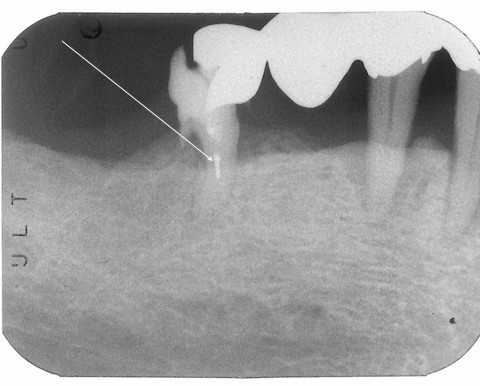

40代女性、右上6、温冷痛+、時々痛い他院(よそ)で神経を取るといわれたので当院(うち)に来られた。露髄(神経が出ている)してて痛みがあれば神経は治る見込みがないので、罰髄>被せとなるのが一般の治療方針だが、そうでもない。というかほとんどそんなことはしなくても良い。矢印部分が神経が露髄してる部分だが、α-TCPセメントで直接覆髄してCRで再建すれば問題ない。では時系列でどうぞ

2021.09.23